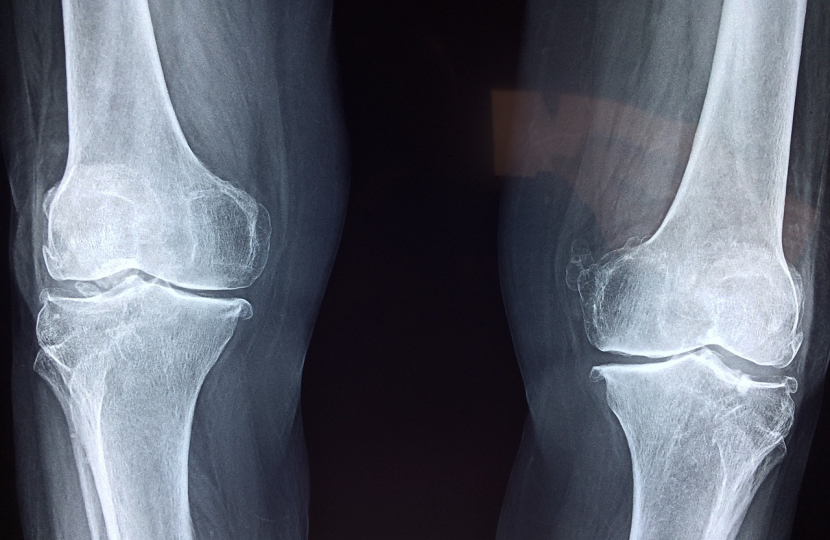

bones

However, as a close observer of the many grave issues confronting our health services today, I have been impressed recently by the determined efforts of the Royal Osteoporosis Society to direct public attention to the very patchy provision of fracture liaison services in our country. It is an urgent and pressing matter that calls for action by the Government in this new Session.

Thanks to this campaign, we now know that fracture liaison  services, the world standard for diagnosing osteoporosis at an early stage, are not provided by  half of all NHS trusts. In areas where they are not available, those with fractures generally receive treatment in A &E departments, but they are often not told that osteoporosis was the cause,

It is a common misconception that action to tackle osteoporosis mainly involves preventing hip fractures in people over the age of 70. Osteoporosis and fractures can have a huge effect on younger people’s professional lives. One in every 12 women over 55 experiences a spinal fracture, rising to one in 10 for those over 60.

We should all be deeply troubled by the extent to which osteoporosis goes undiagnosed. Some 2.6 million women and men endure the effects of  undiagnosed spinal fractures. They inevitably find themselves reducing their hours of work or being pushed into early retirement due to vague back pain, which is often the result of undetected osteoporotic fractures.

This is borne out in the statistics. Every year in England, there are around 67,000 fractures in the working-age population. As a result, some 2.6 million working days are lost every year, according to the International Osteoporosis Foundation. And yet drug therapies can reduce rates of refracture by up to 90 per cent for the most common osteoporotic fractures.

Both business leaders and trade unions are firmly behind this year’s hugely informative ‘ Better Bones’ campaign in its call for universal fracture liaison services.  How can that be achieved? The Government are being urged by the experts in this field to establish a transformation fund to fill the stubborn gaps in existing provision.  Such a fund would enable us to keep up with the rest of the world in diagnosing osteoporosis early, before the disease has the chance to inflict grave damage on individuals and society.